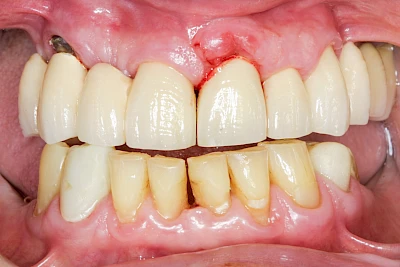

Ist zunächst nur das Zahnfleisch von der Entzündung betroffen, spricht man von Gingivitis. Später, wenn auch der Knochen um die Zähne herum entzündet ist, spricht man von einer Parodontitis. Bei der Parodontitis wird der Knochen nach und nach abgebaut und das Zahnfleisch zieht sich zurück. Die Zahnhälse und Zahnwurzeloberflächen liegen mehr und mehr frei. Die Zähne werden zunehmend lockerer und fallen schließlich aus.